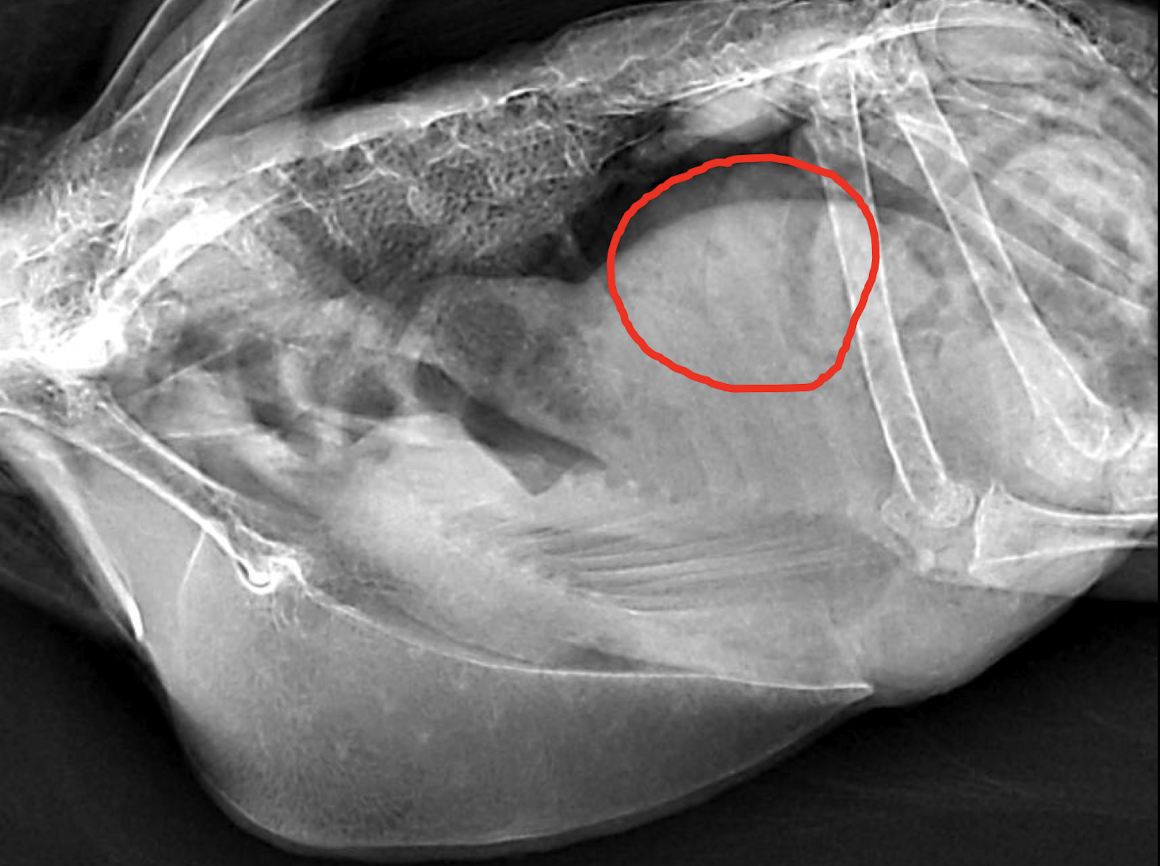

What is wrong?

gonadal mass